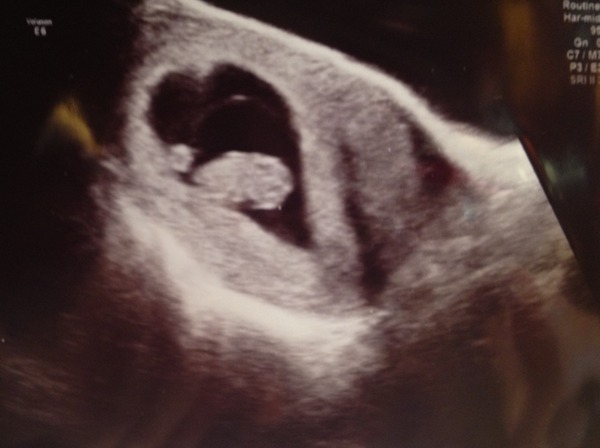

Morning all, i just wanted to update everyone! Firstly thank you for your reassurance last week (i posted about symptoms disappearing). We went for a scan on Sunday and it was money well spent! Baby measuring on time at 9w1d and we seen the heartbeat beating away, baby also wiggled and jumped on screen! So my due dates August 29th hope i can still be part of the September thread :) heres a picture of little bean in his or hers own love heart! :D